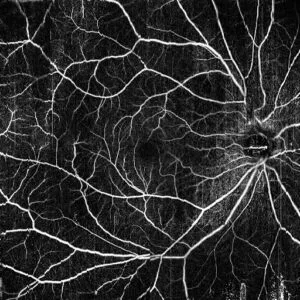

従来と違う新たなOCT(光干渉断層計)を導入し、造影剤を使用しない網膜の血管撮影(OCTアンギオグラフィー)が可能になりました。

OCTAでは網膜内の動きのある部分とない部分とに分けて動きのある部分だけを抽出します。

網膜内で動きのある部分は血管内の血流のみのため、この差から網膜の血管の形態を確認することができ、造影剤を使用した撮影に近い画像を得ることが可能です。

これによって、加齢黄斑変性、糖尿病網膜症などでみられる網膜新生血管、網膜に血が通わない無血管野、血管閉塞などの位置を特定することができ、レーザー治療等の施行の判断が容易になります。